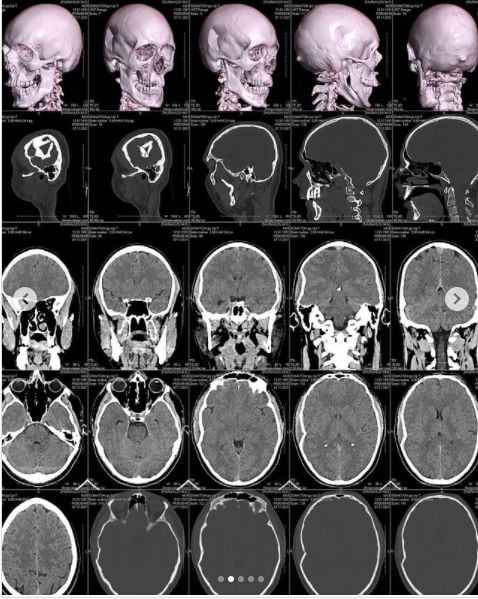

Композитора та музичного продюсера гурту KAZKA Миколу Журавльова побили у під’їзді його ж будинку. Лікарі діагностували переломи черепа та носу, а також травми підборіддя.

Каже, що вже переніс операцію з видалення пошкоджених кісток черепа. Надалі йому доведеться робити ще одну – ставитимуть титанову пластину.

"Хірург сказав, що з такими травмами зазвичай до лікарні приїжджають вже у комі. Але ми з Діаною ще 12 годин після травми їздили по всьому Києву робили обстеження, комп'ютерну томографію та інше", – пише Журавльов.

Згідно з висновками лікарів, у музиканта імпресійний перелом склепіння черепа в області скроневої та тім'яної кісток із вдавленням уламка у праву скроневу частку та перелом носових кісток.